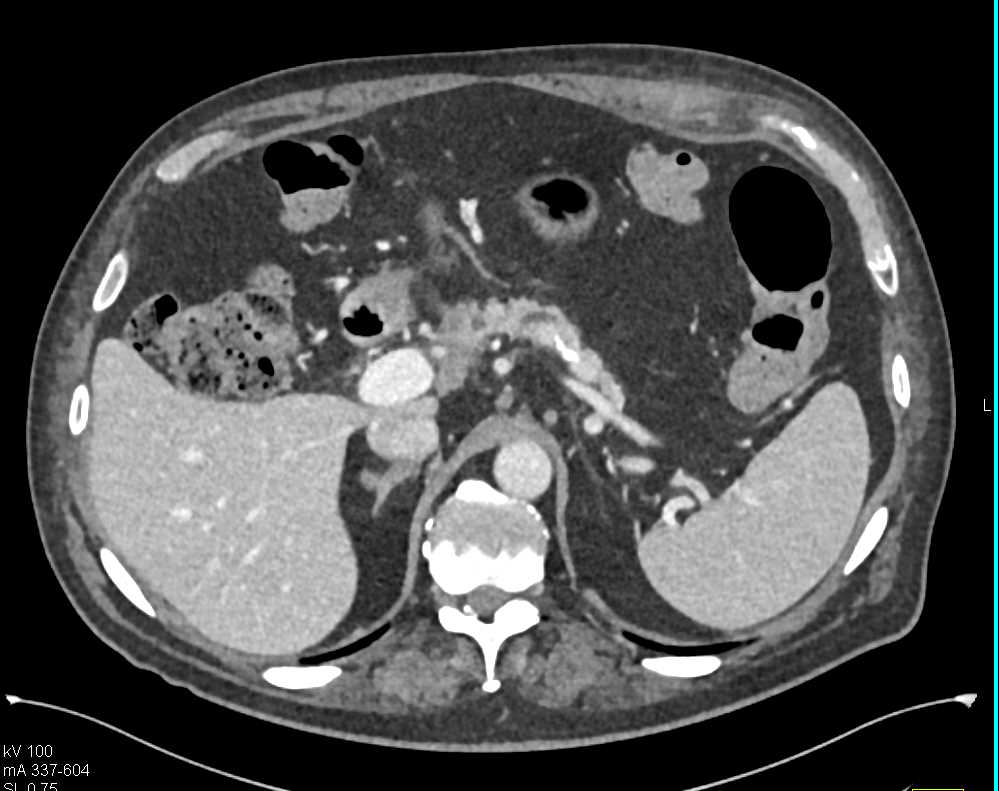

Carcinoma Head of the Pancreas